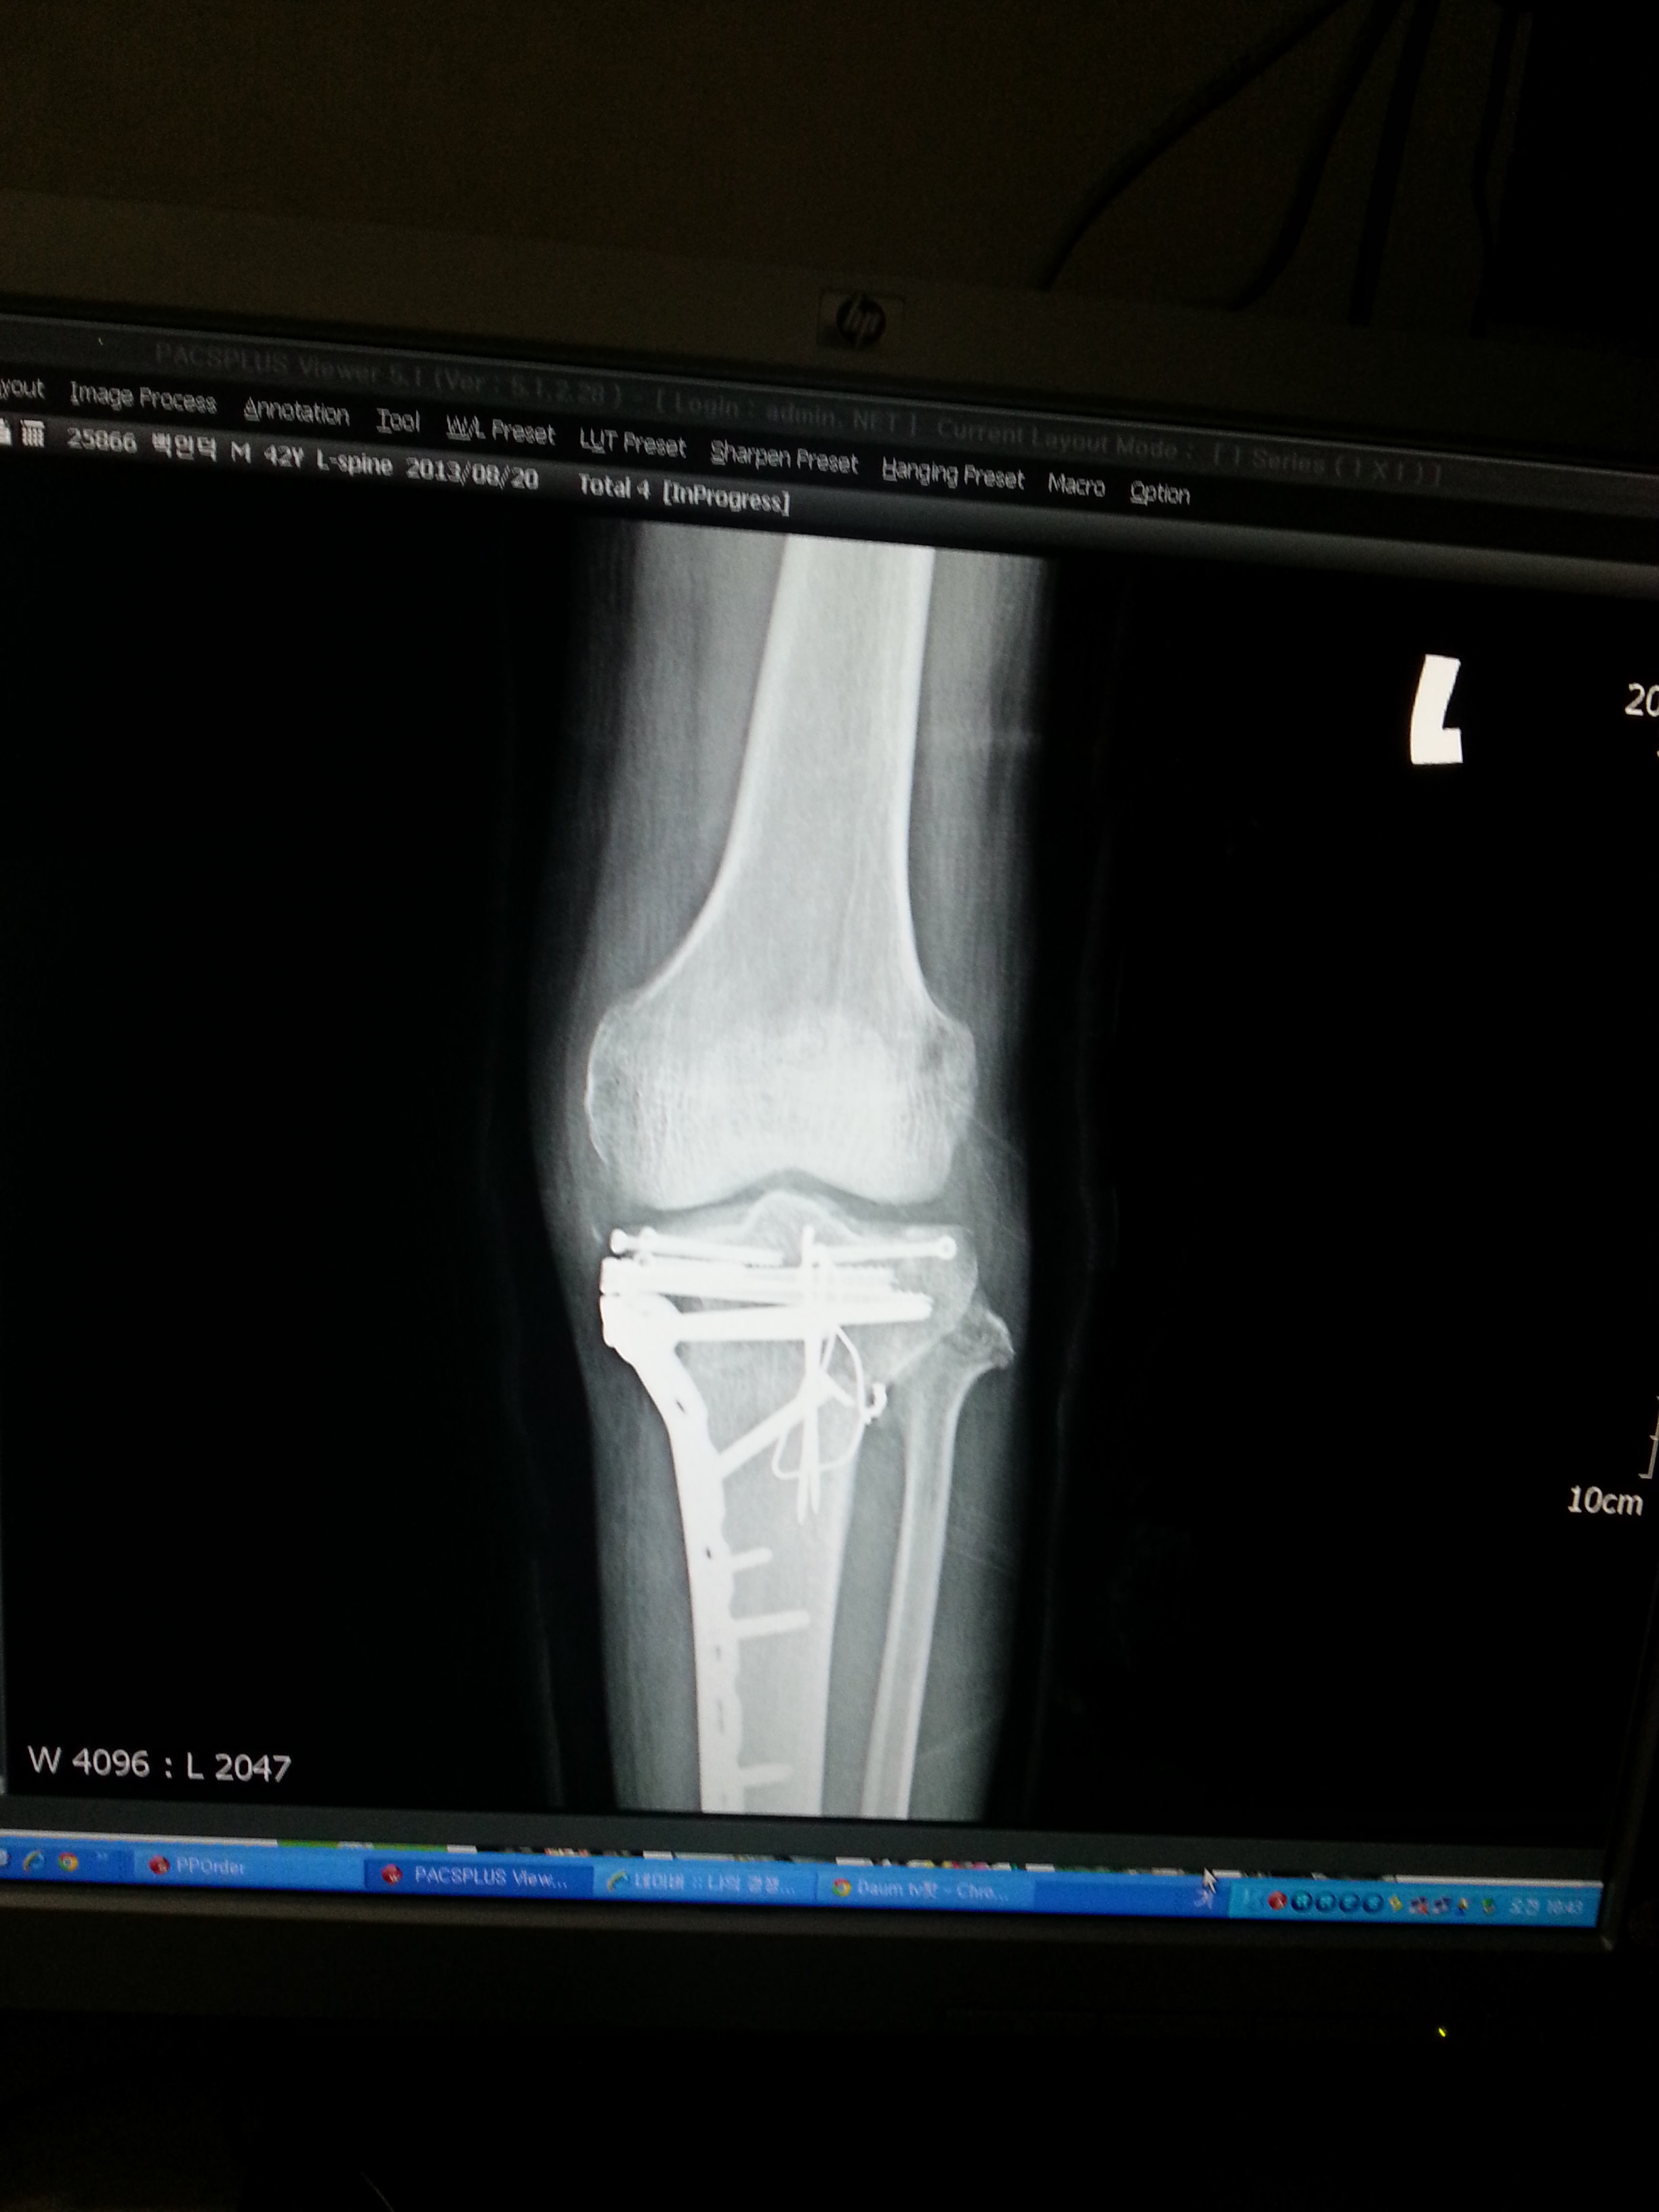

오토바이를 타고 가는데...배달하는 어린 아이가 나를 들이 받아서...

나는 그날 이후로 장애인이 되어 버렸다..

주요한건..오늘자..아직도 이 핀을 제거하지 못하고..

아직 정상적인 상태가 아니란것...